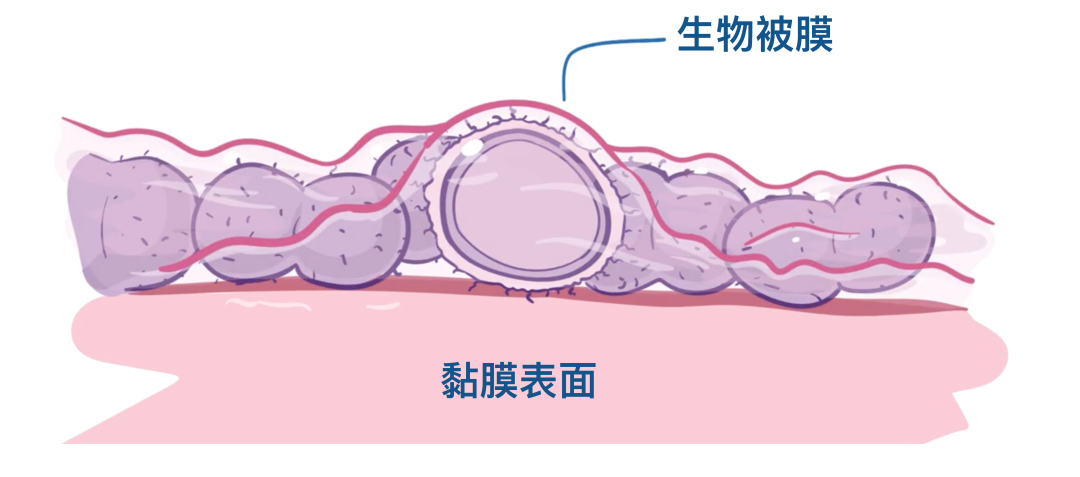

一旦附着在如鼻咽部或中耳等黏膜表面,肺炎链球菌就能繁殖并形成生物膜。

生物膜基本上就是一层由胞外多糖(EPS)组成的胶状物质,肺炎链球菌就生活和繁殖在其中。

如果把生物膜比作果酱,那么里面的细菌就像果酱里的籽,而果酱的其余部分就是这些多糖物质。

生活在生物膜中的细菌能够躲避免疫系统和抗生素的攻击,甚至还能在其中交换耐药基因,可谓非常狡猾。